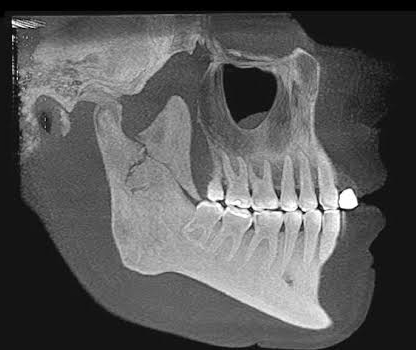

Fratura do Processo coronóide